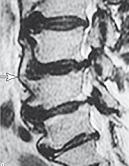

МРТ № 40

МРТ № 41

На МРТ № 40 наблюдается типичный пример развития стеноза второго типа в шейном отделе позвоночника. И аналогичная картина, только, в поясничном отделе позвоночника, отображена на МРТ № 41